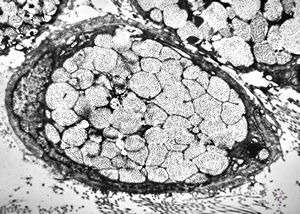

F, 24y. | molluscum contagiosum … virions

F, 24y. | molluscum contagiosum

F, 24y. | molluscum contagiosum

F, 24y. | molluscum contagiosum … virions